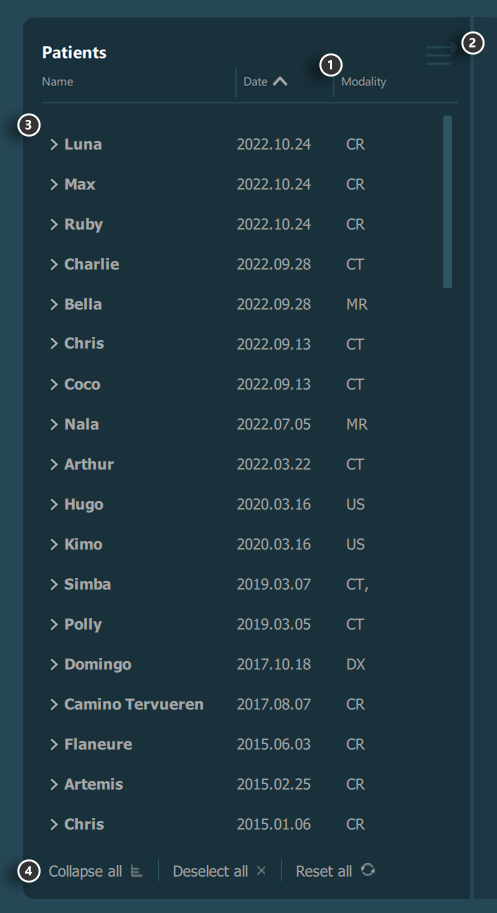

Study List¶